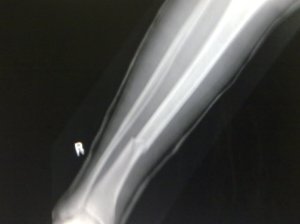

Marty suffered a badly broken leg.